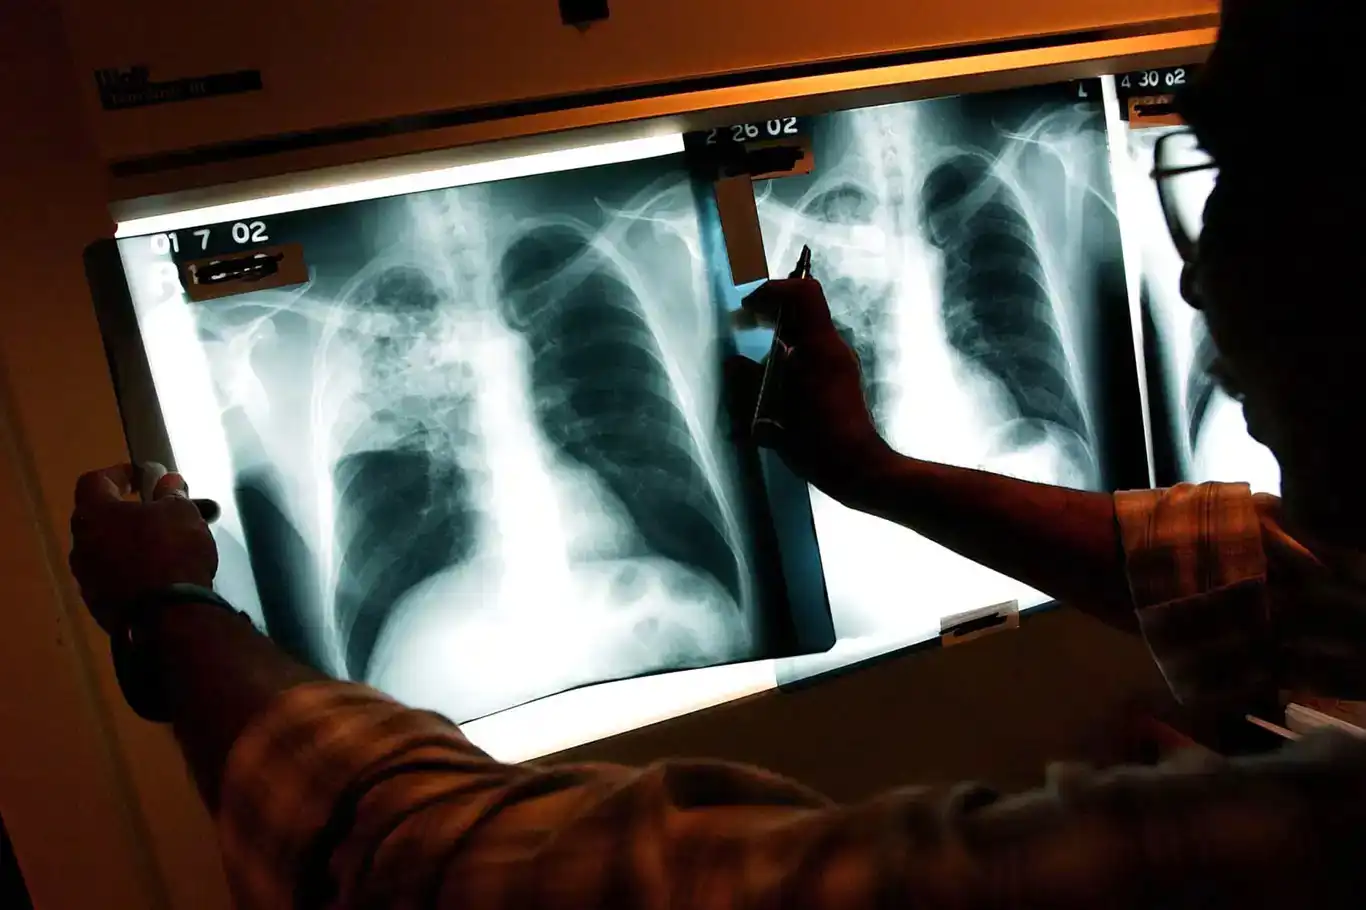

أوضح المدير الإقليمي لمنظمة الصحة العالمية في أوروبا، هانس كلوغه، أن مرض السل، وهو أكثر الأمراض المعدية فتكاً في العالم، يتسبب سنوياً في وفاة نحو مليون شخص.

أكد المدير الإقليمي لمنظمة الصحة العالمية في أوروبا، هانس كلوغه، أن مرض السل يعد أكثر الأمراض المعدية فتكاً في العالم، حيث يتسبب سنوياً في وفاة نحو مليون شخص.

وأشار كلوغه إلى أن مقاومة الأدوية، والتزامن بين السل وفيروس نقص المناعة البشرية، وعدم المساواة في الحصول على الرعاية الصحية، إضافة إلى التمويل غير الكافي، يزيدان من تفاقم الأزمة.

وكانت المنظمة قد أعلنت في تقريرها العالمي للسل لعام 2025، الصادر في 12 تشرين الثاني/ نوفمبر، أن أكثر من 1.2 مليون شخص فقدوا حياتهم بسبب السل في 2024، فيما تأثر حوالي 10.7 مليون شخص بهذا المرض.

وقال المدير العام للمنظمة، تيدروس أدهانوم غيبريسوس: "إن التقدم المحرز ليس انتصاراً"، مؤكداً أن استمرار وفاة أكثر من مليون شخص سنوياً بسبب مرض يمكن الوقاية منه وعلاجه يمثل أمراً غير إنساني، مشيراً إلى أن المنظمة تعمل مع الدول لتسريع الجهود نحو القضاء على السل بحلول عام 2030.

ويعد السل مرضاً معدياً يصيب الرئتين وينتقل عن طريق الهواء من شخص لآخر، وينجم عن بكتيريا Mycobacterium Tuberculosis، وهو قابل للعلاج والوقاية بواسطة التطعيم. (İLKHA)